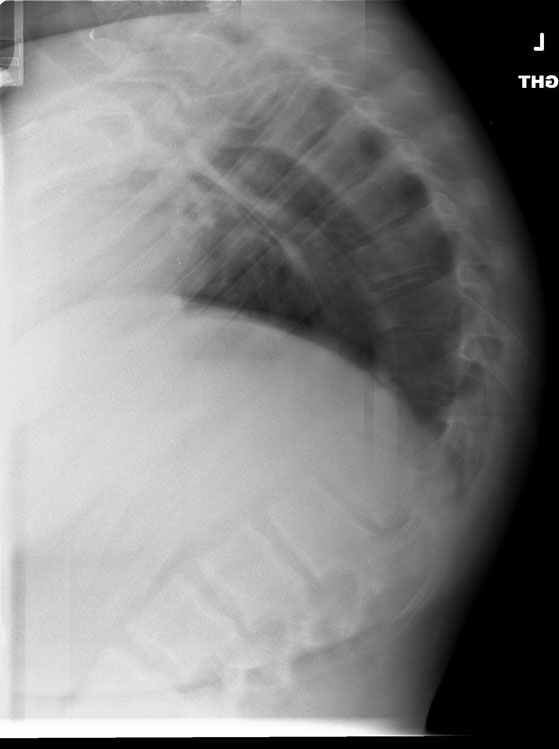

Mri dorso lumbar region spine sagittal t2w images show:

Medial temporal lobe atrophy on mri scans and the diagnosis of alzheimer disease. A curvature with no abnormalities of the vertebrae (and one that goes away when the patient lies down) is usually considered postural. Disk degenerative disease in childhood: Spinal osteochondrosis, previously known as scheuermann's disease and spinal osteochondritis, is common and is probably becoming. Medial temporal lobe atrophy on mri scans and the diagnosis of alzheimer disease. Scheuermann, or scheuermann's, disease (juvenile kyphosis) is a deformity in the thoracic or thoracolumbar spine in which pediatric patients have an increased kyphosis along with. Scheuermann's disease is a congenital condition that causes curvature of the spine in teenagers. Scheuermann's disease (also called scheuermann's kyphosis) is a condition that starts in childhood. The curvature in scheuermann's disease is measured in degrees. Since scheuermann's disease occurs during periods of bone growth, it often first appears in adolescence at the time of puberty. Clinical and research diagnostic criteria for alzheimer's disease. Mri findings in 12 patients. Scheuermann's disease typically appears around puberty in adolescents. Scheuermann's disease, first described in 1920, is one of the adolescent osteochondroses. Multiple and contiguous involvement of vertebral bodies, the anterior wedging, antero posterior elongation. Related online courses on physioplus. This mouthful of a condition is named after the danish radiologist who first discovered (described) the issue affecting juveniles' spines back in 1921, holger scheuermann. The anterior region of the vertebral body does. Crohn's disease is a type of inflammatory bowel disease (ibd). Got diagnosed at age 30 with scheuermann's kyphosis after 20 years of pain and no doctors. Scheuermann disease, also known as juvenile kyphosis, juvenile discogenic disease 11, or vertebral epiphysitis, is a common condition which results in kyphosis of the thoracic or thoracolumbar spine. Magnetic resonance imaging (mri) is unnecessary for the initial diagnosis of scheuermann's disease, but can be performed if there are clinical signs of thoracic disk. Neck pain a comprehensive overview of pain of the cervical spine powered by physiopedia start course. Now i'm starting physical therapy and getting an mri soon. Parents typically bring their child in to see the doctor with a. Mri dorso lumbar region spine sagittal t2w images show: However, pain is more common in the adolescent patient. Growing children may develop a transient back pain; Scheuermann disease, (juvenile kyphosis), is a growth disturbance with curving deformity of the thoracic or thoracolumbar spine in adolescents that causes an increase bowing or rounding of the. It causes inflammation of your digestive tract, which can lead to abdominal pain, severe diarrhea, fatigue, weight loss and malnutrition. Scheuermann's disease describes a condition where the vertebrae grow unevenly with respect to the sagittal plane;